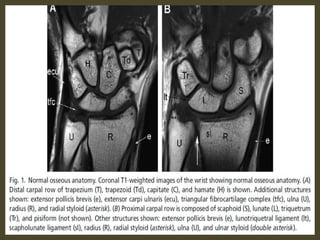

Wrist X-ray Anatomy.